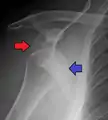

A diagnosis of shoulder dislocation is often suspected based on the person's history and physical examination. Radiographs are made to confirm the diagnosis. Most dislocations are apparent on radiographs showing incongruence of the glenohumeral joint. Posterior dislocations may be hard to detect on standard AP radiographs, but are more readily detected on other views. After reduction, radiographs are usually repeated to confirm successful reduction and to detect bone damage. After repeated shoulder dislocations, an MRI scan may be used to assess soft tissue damage. In regards to recurrent dislocations, the apprehension test (anterior instability) and sulcus sign (inferior instability) are useful methods for determining predisposition to future dislocation.

A Hill–Sachs lesion is an impaction of the head of the humerus left by the glenoid rim during dislocation.[6] Hill-Sachs deformities occur in 35–40% of anterior dislocations. They can be seen on a front-facing X-ray when the arm is in internal rotation.[9] Bankart lesions are disruptions of the glenoid labrum with or without an avulsion of bone fragment.

Posterior (backward)

Posterior dislocations are uncommon, and are typically due to the muscle contraction from electric shock or seizure.[6] They may be caused by strength imbalance of the rotator cuff muscles. People with dislocated shoulders typically present holding their arm internally rotated and adducted, and exhibiting flattening of the anterior shoulder with a prominent coracoid process.

Posterior dislocations may go unrecognized, especially in an elderly person[12] and in people who are in the state of unconscious trauma.[13] An average interval of 1 year was noted between injury and diagnosis in a series of 40 people.[14]